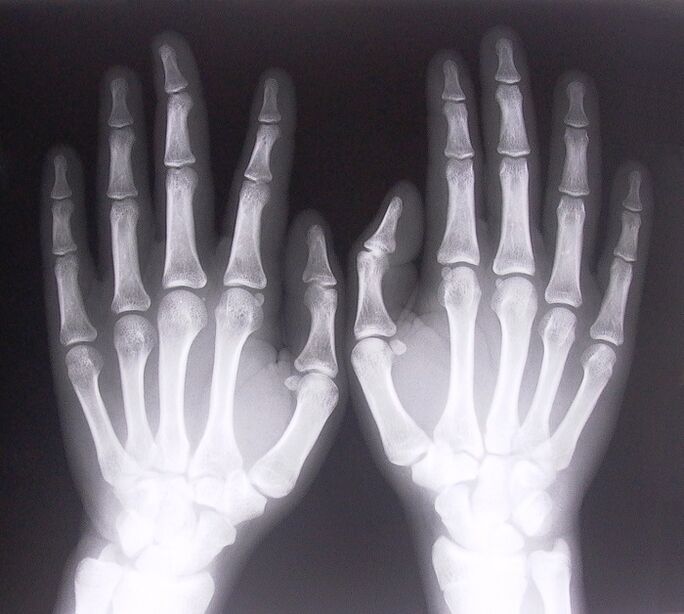

- Stenosing ligamentitis.To identify the cause of the disease, an x-ray is required.Symptoms are typical: painful movement of the hand, rotation of the clenched palm.Also, during extension, clicks are often heard.

- Take x-rays.